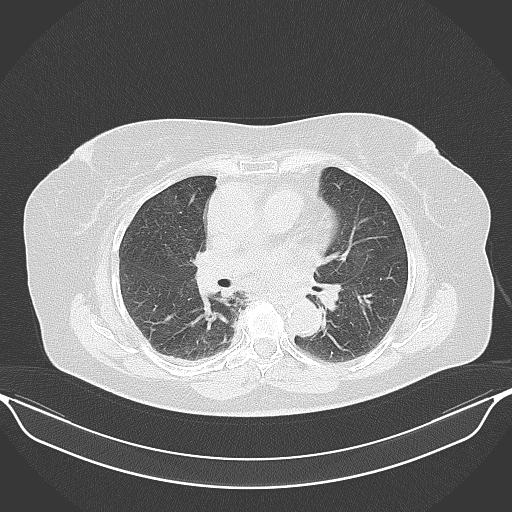

Original NATIVE CT scan (input)

Full window (WL 1023.5, WW 4095 β†’ Low βˆ’1024, High +3071)

Lung window (WL -600, WW 1500 β†’ Low βˆ’1350, High +150)